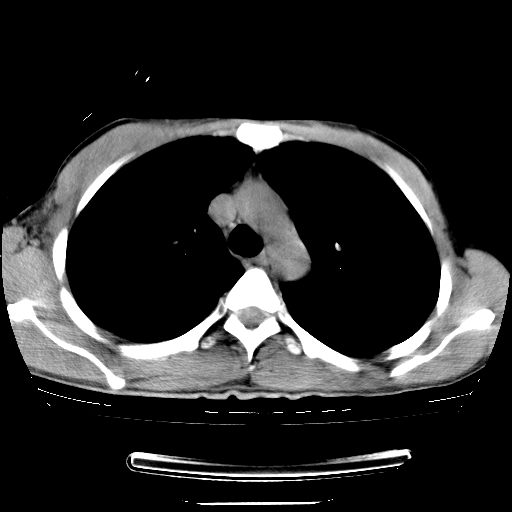

以下是引用dyqct在2008-4-29 8:43:00的发言:[br][br] 支持右侧胸腔包裹性积血。闭式引流管是不是插的太深了?

以下是引用zjzjr在2008-4-29 14:11:00的发言:[br]支持右侧胸腔包裹性积血。闭式引流管是不是插的太深了?胸腔引流,引流管快进入纵隔了.